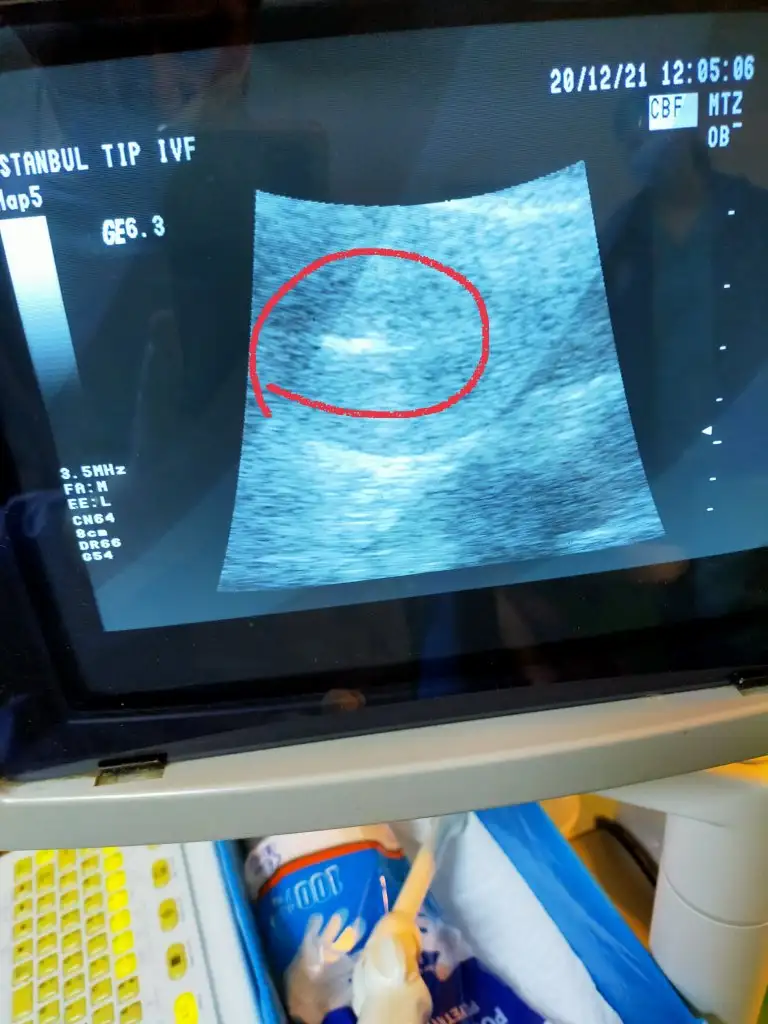

😅😅😅cnm ben transfer günü fotoğrafını çekip verdiler o kadar çok duygulandım ki anlatan çünkü ilk defa bebisimigördüm 🤩🤩🤩🤩😍😍😍😍

Evet rahme biraktiklari an çektiler onunla yatıp onunla kalkıyorum 😊😍

Böyleydi benimde 🥺🥺🥺🥺 o zaman o kadar çok ağladım ki anlatılamaz duygu resmen

Bebisime bakarak 🤩🤔